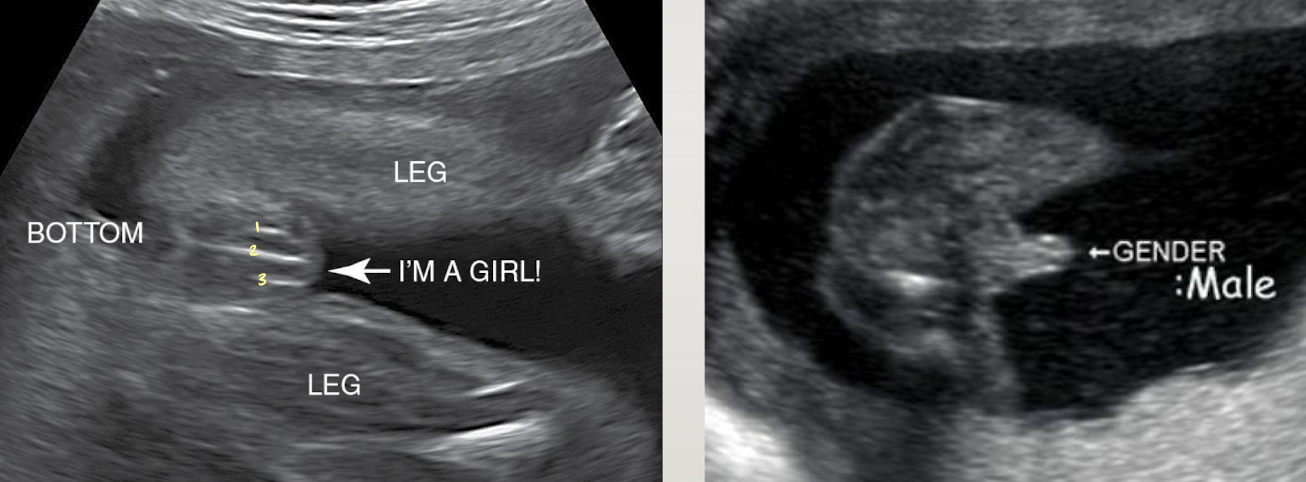

genitalia

sexual characteristics develop between 9-12 weeks

fetal testes produce androgens that cause masculinization of external genitalia (baby start as a girl)

fetal external genitalia can be definitively identified with US after 18wks

SONO: genitalia (male vs. female)

male

both scrotum and penis identified

“turtle sign”

female

vulva/labia lips identified

“three-line sign”

“hamburger sign”